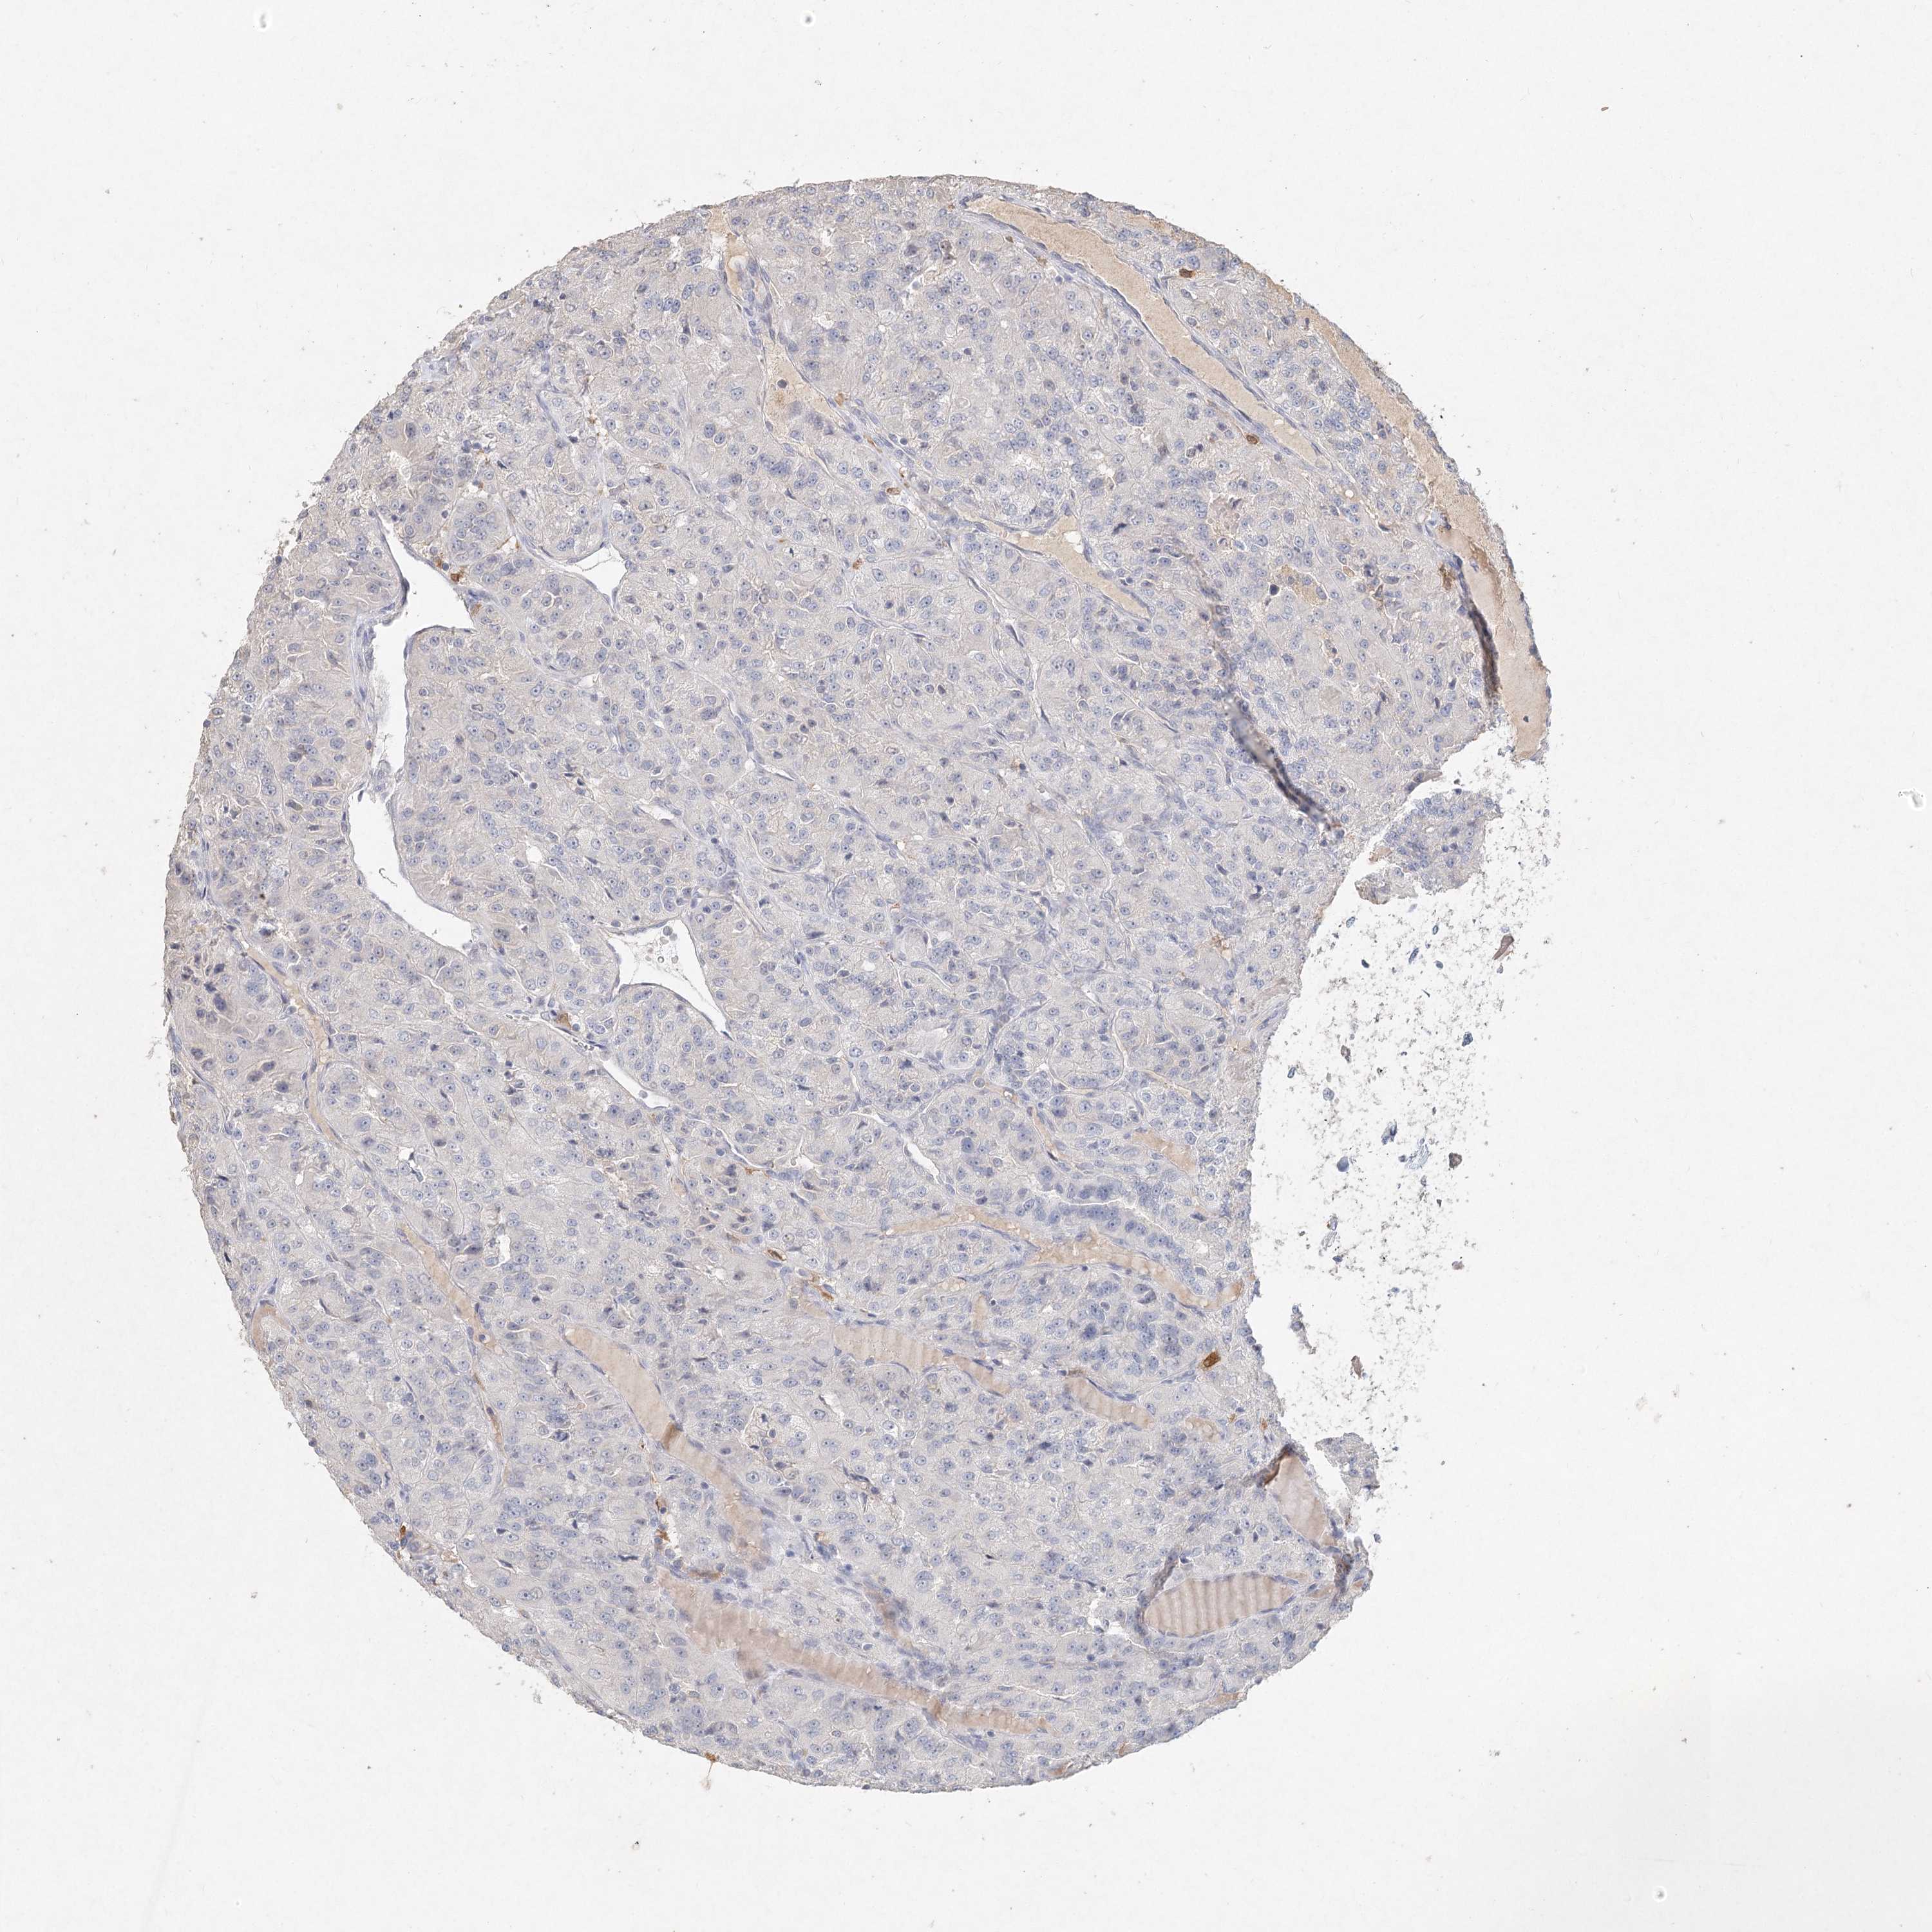

CANCER RENAL CANCER Show tissue menu

KICH TCGA KIRC TCGA KIRC VALIDATION KIRP TCGA PROTEIN RCC CPTAC PROTEIN EXPRESSION